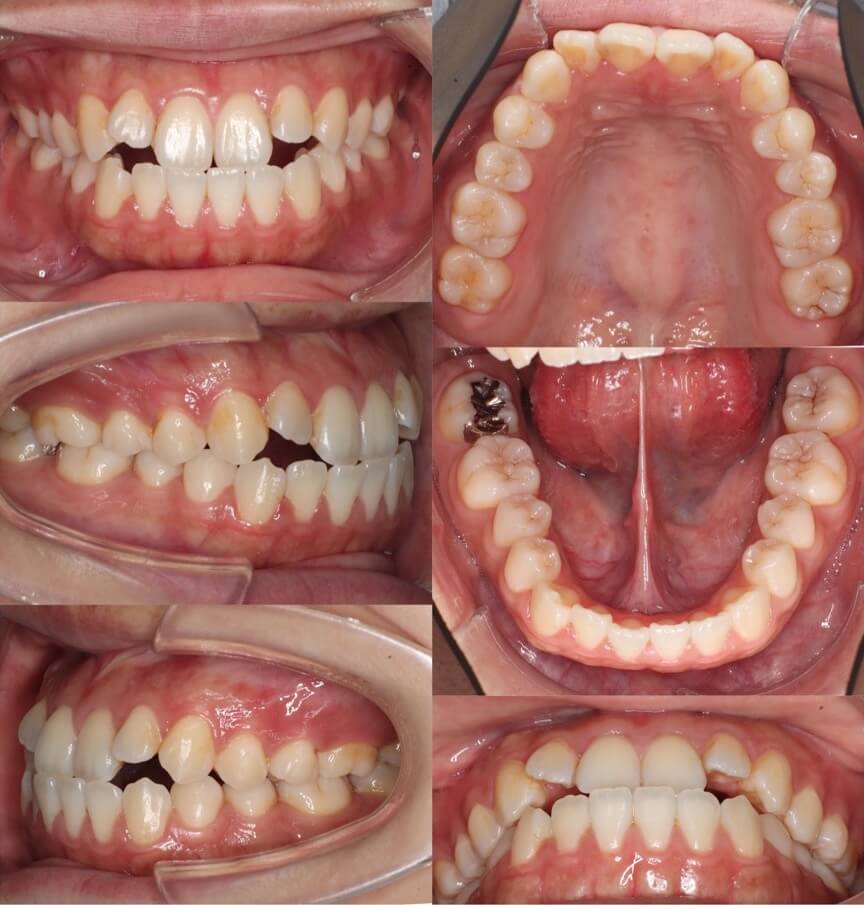

20代女性・マウスピース型装置・非抜歯

<症例概要>

主訴:受け口

年齢・性別:20代女性

住まい:千葉県鎌ヶ谷市

症状:下顎前突・反対咬合

治療方針:上顎拡大・下顎歯列後方移動・IPR

治療装置:マウスピース型矯正装置(アライナー装置)

治療期間:2年2か月

アライナー枚数:60+38+21ステージ

リテーナー:上下クリアタイプ

治療費用:990,000(税込)

代表的副作用:痛み・治療後の後戻り・歯根吸収・歯髄壊死・歯肉退縮

【治療シミュレーション】

III級ゴムを使用して、奥歯から後方移動させ、最後に前歯大きく後ろに引っ込めます。

右半分の前歯のかみ合わせが反対咬合になっているケースです。また下あごの形の非対称もあり正中線も上下であっていません。下の歯並びをIPRを加えながら後方移動させることで前歯を後ろに押し込みかみ合わせを改善しました。